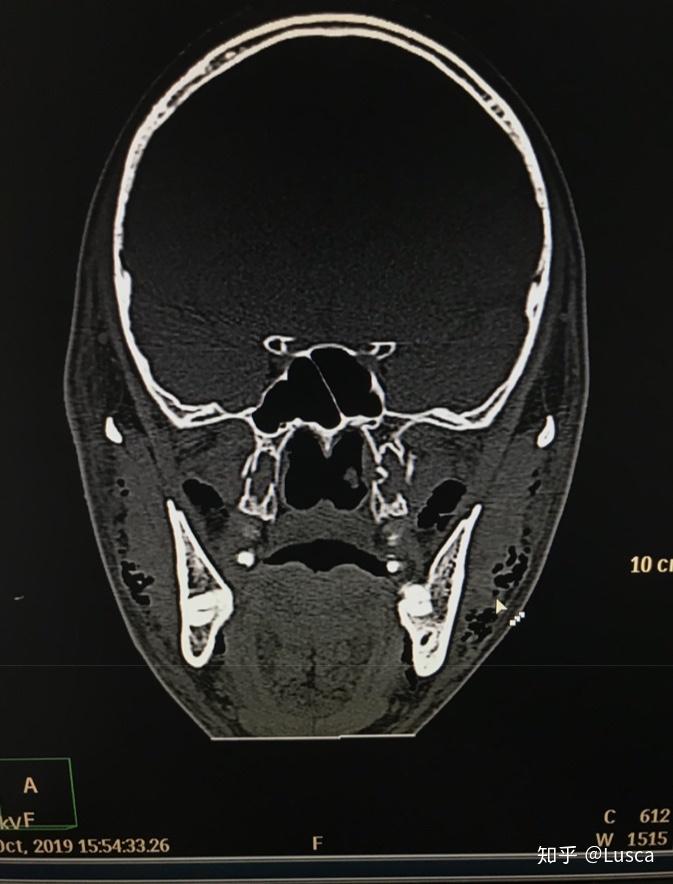

诊断 处理 上颌骨lefort-i骨折,下颌骨颏部骨折.